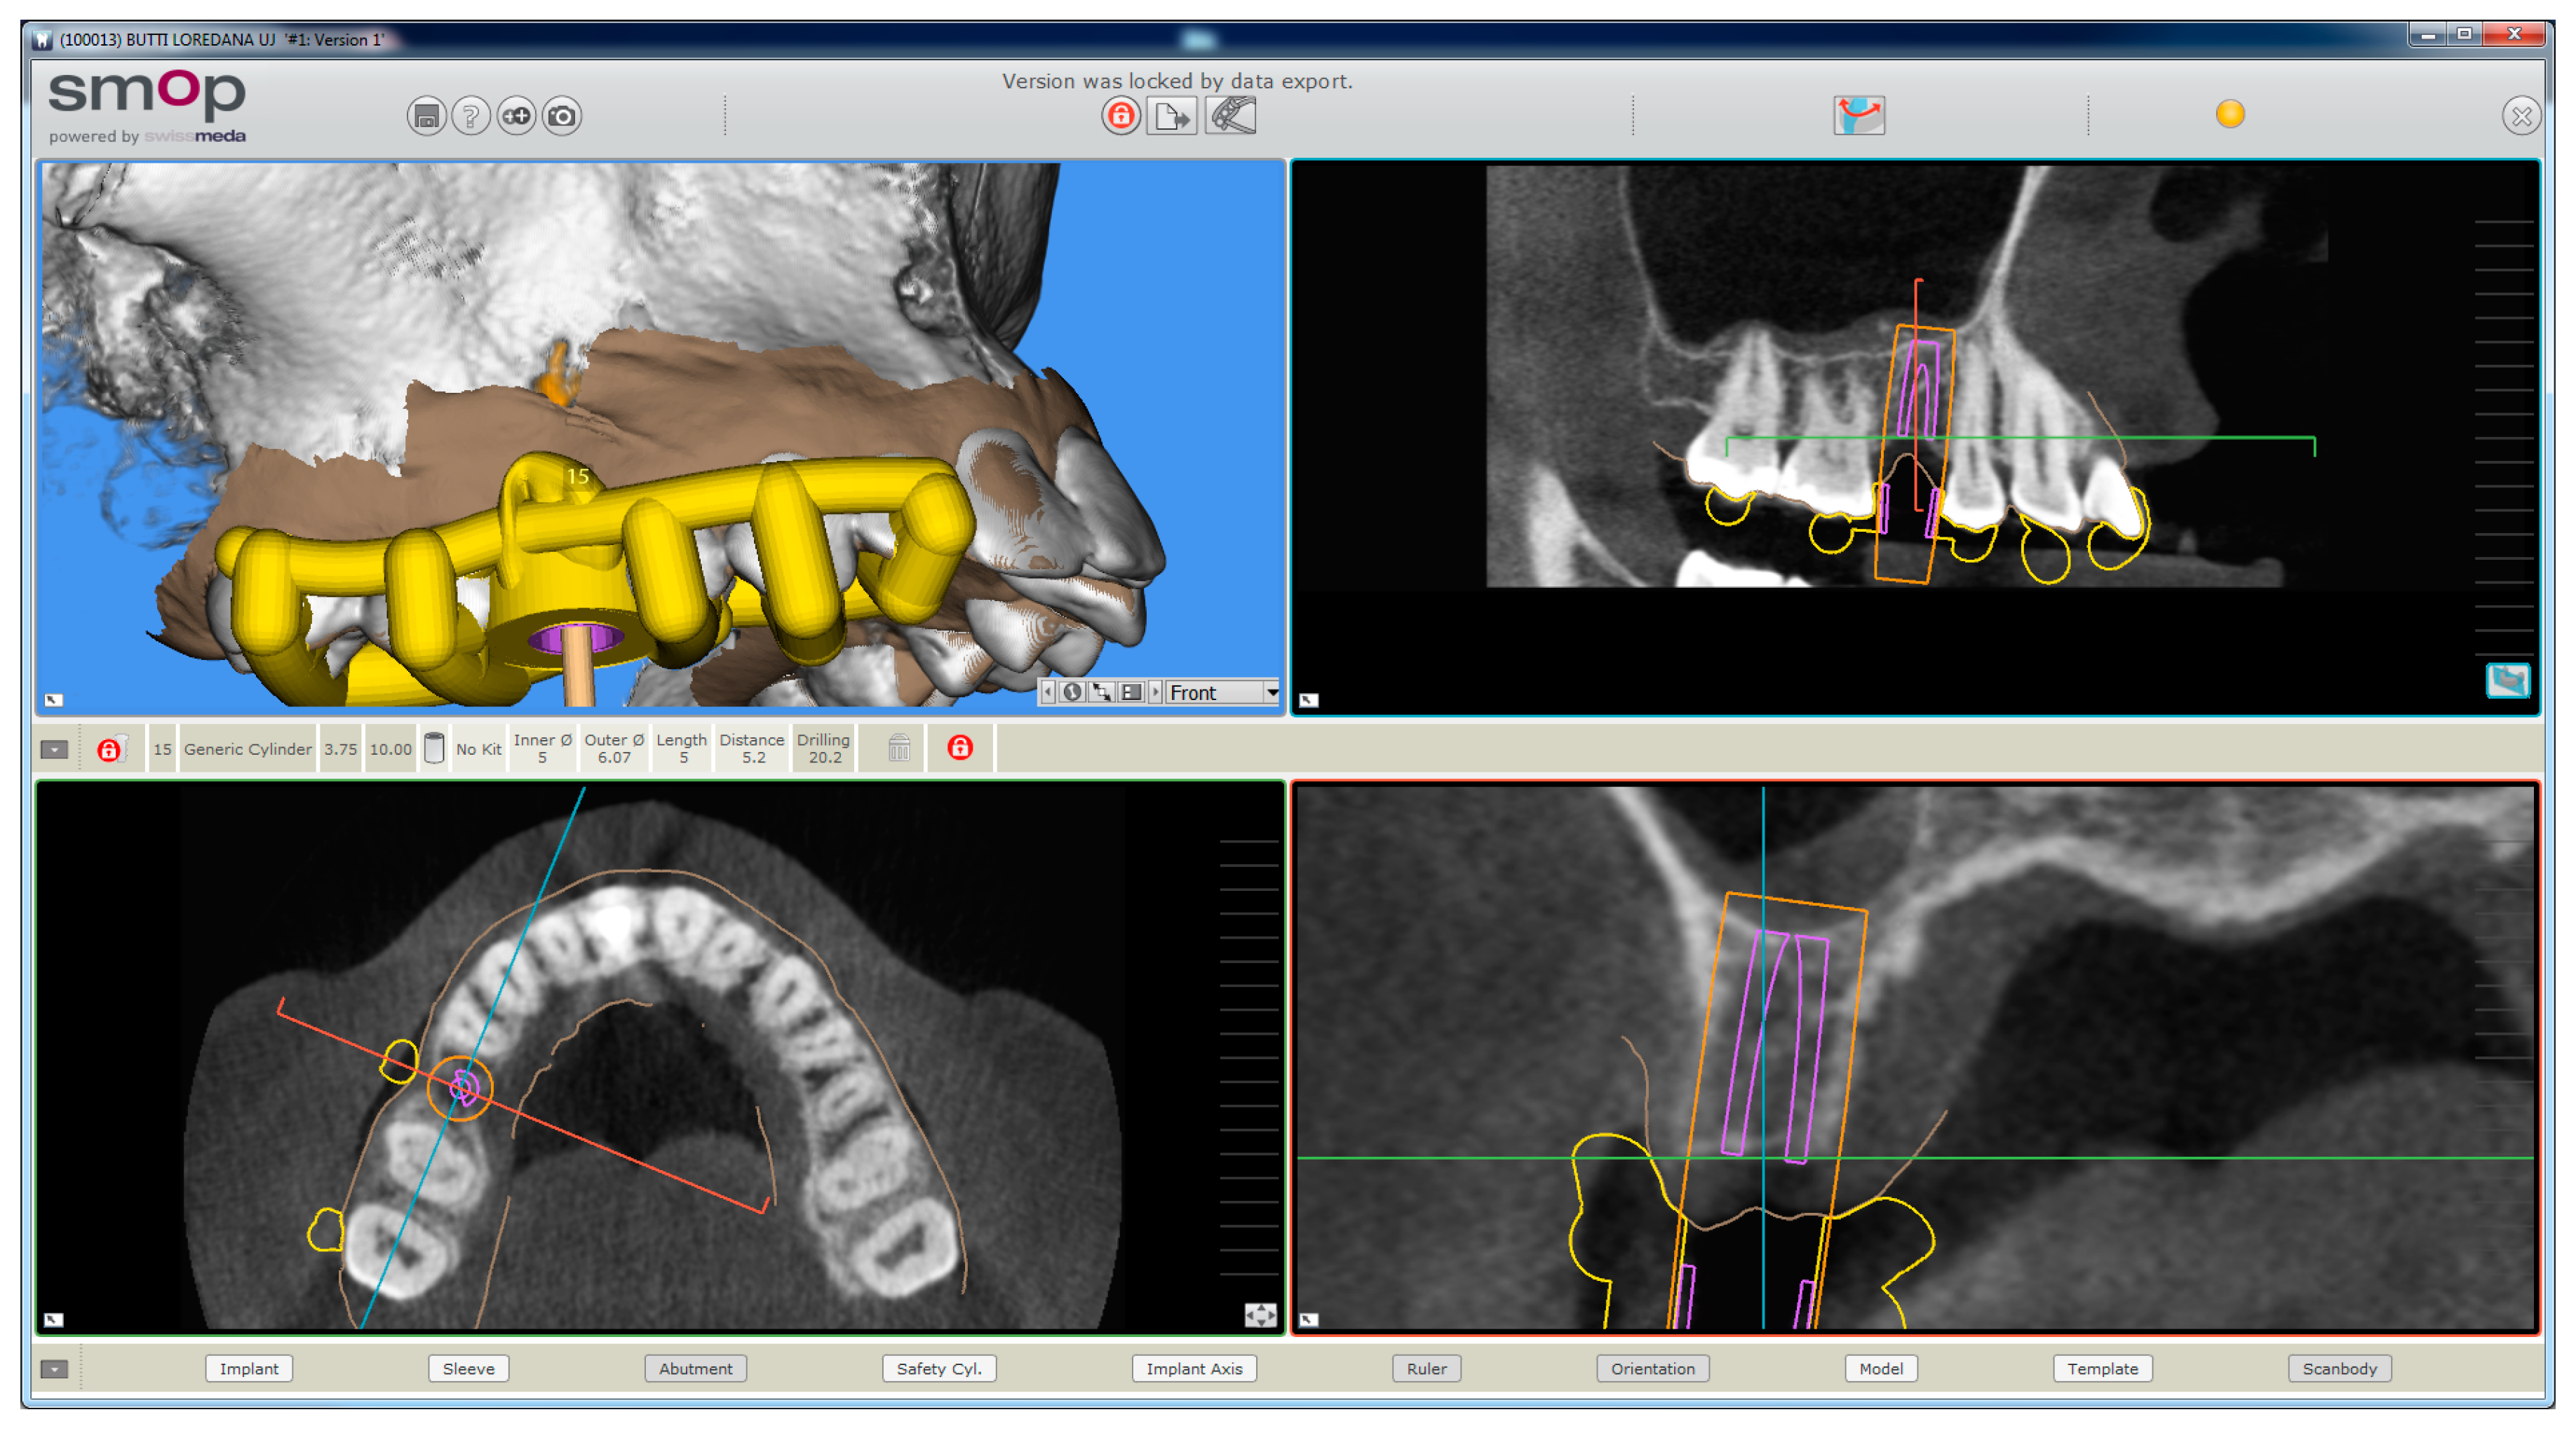

The planning of the case involved the use of two different sets of software: A prosthetic CAD (computer-assisted-design) (EXOCAD®, Darmstad, Germany) for the virtual wax-up and a surgical CAD (SMOP®, Swissmeda, Baar, Switzerland) for 3D planning of implant placement and the design of the surgical template (Figure 3).

Figure 3.

The implant is planned with the aid of a guided surgery software (SMOP®, Swissmeda, Baar, Switzerland). A 3.75 mm × 10 mm implant (BT Safe Bone Level®, BTK, Dueville, Italy) is therefore planned.

In the order, the .STL files deriving from the intraoral scan were imported into the prosthetic CAD, where the virtual waxing of the restoration (single crown or partial fixed prosthesis) was carried out, taking into account the volumes, shapes, and interproximal contacts of the adjacent and occlusal teeth with the antagonist arch. The file of the waxing was thus saved in a special folder, always as .STL, in order to be opened in the surgical CAD before planning the implant placement. At this point, the operator opened the surgical CAD software by importing the DICOM files derived from the patient’s CBCT. The software presented the different reconstruction planes (axial, coronal, and sagittal) and allowed the importation of the intraoral scan file (.STL) that was superimposed on the reconstruction of bone from CBCT. The superimposition was performed with care, first for points and then for surfaces, and controlled in each section. This phase was the most delicate of all, since a possible overlap error can undermine the planning and therefore the positioning of the fixture in the exact desired position. Once the quality of the overlap between intraoral scan and bone reconstruction by CBCT was carefully checked and verified, the operator identified the anatomical structures of risk (alveolar inferior nerve, maxillary sinus) and the design of the panoramic curve, in order to obtain the desired cross sections. The operator imported the .STL file of the diagnostic wax-up and proceeded to plan an implant of a length and a diameter appropriate to the recipient site, taking into accounts the residual bone anatomy and the important information derived from the wax-up. The implant was therefore planned in the best possible position, and prosthetically guided in relation to the residual bone anatomy. Particular attention was paid to the position and inclination of the fixture and its compatibility with the prosthetic emergence. In the case of patients requiring treatment with more than one implant, the same operations were repeated for each of the selected fixtures. At this point, parametric instruments allowed the clinician to establish the distance between the sleeve and the implant shoulder, depending on the height of the available gingiva: In accordance, from the length of the selected implant, and from the height of the sleeve (5 mm in the present study) derived the data related to the drilling depth, a key element in the surgical phase. Furthermore, the parametric tools of the software made it possible to adjust the width of the outside diameter of the hole in the template, for the insertion and fixation of the sleeve.